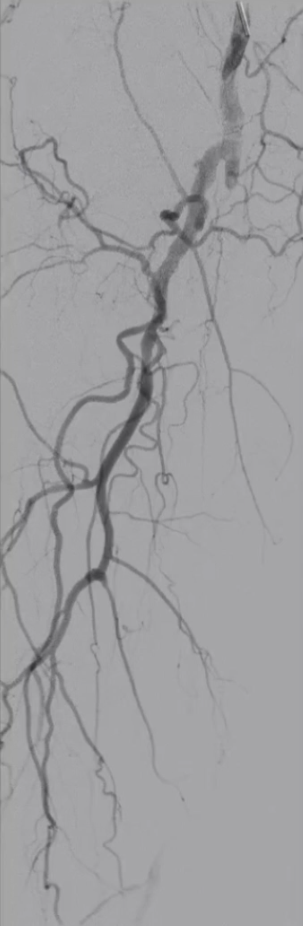

手术结果:

血流通畅,解剖与功能双重改善

最终造影显示:支架定位准确、形态良好,股浅动脉、腘动脉及膝下动脉显影清晰,血流通畅。